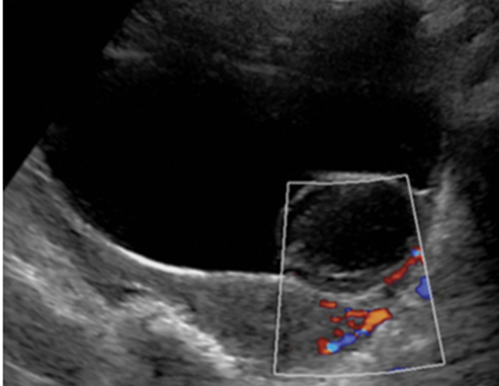

左卵巢囊腺瘤声像图:囊性肿块嵌入在膀胱腔内,运用嵌入器官征思维方法,提示该囊性肿块来源于膀胱之外